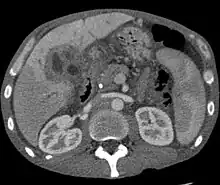

Ultrasound of the liver and biliary tree is often used as the initial imaging modality in people with suspected obstructive jaundice.[49][50] Ultrasound can identify obstruction and ductal dilatation and, in some cases, may be sufficient to diagnose cholangiocarcinoma.[51] Computed tomography (CT) scanning may also play an important role in the diagnosis of cholangiocarcinoma.[52][53][54]